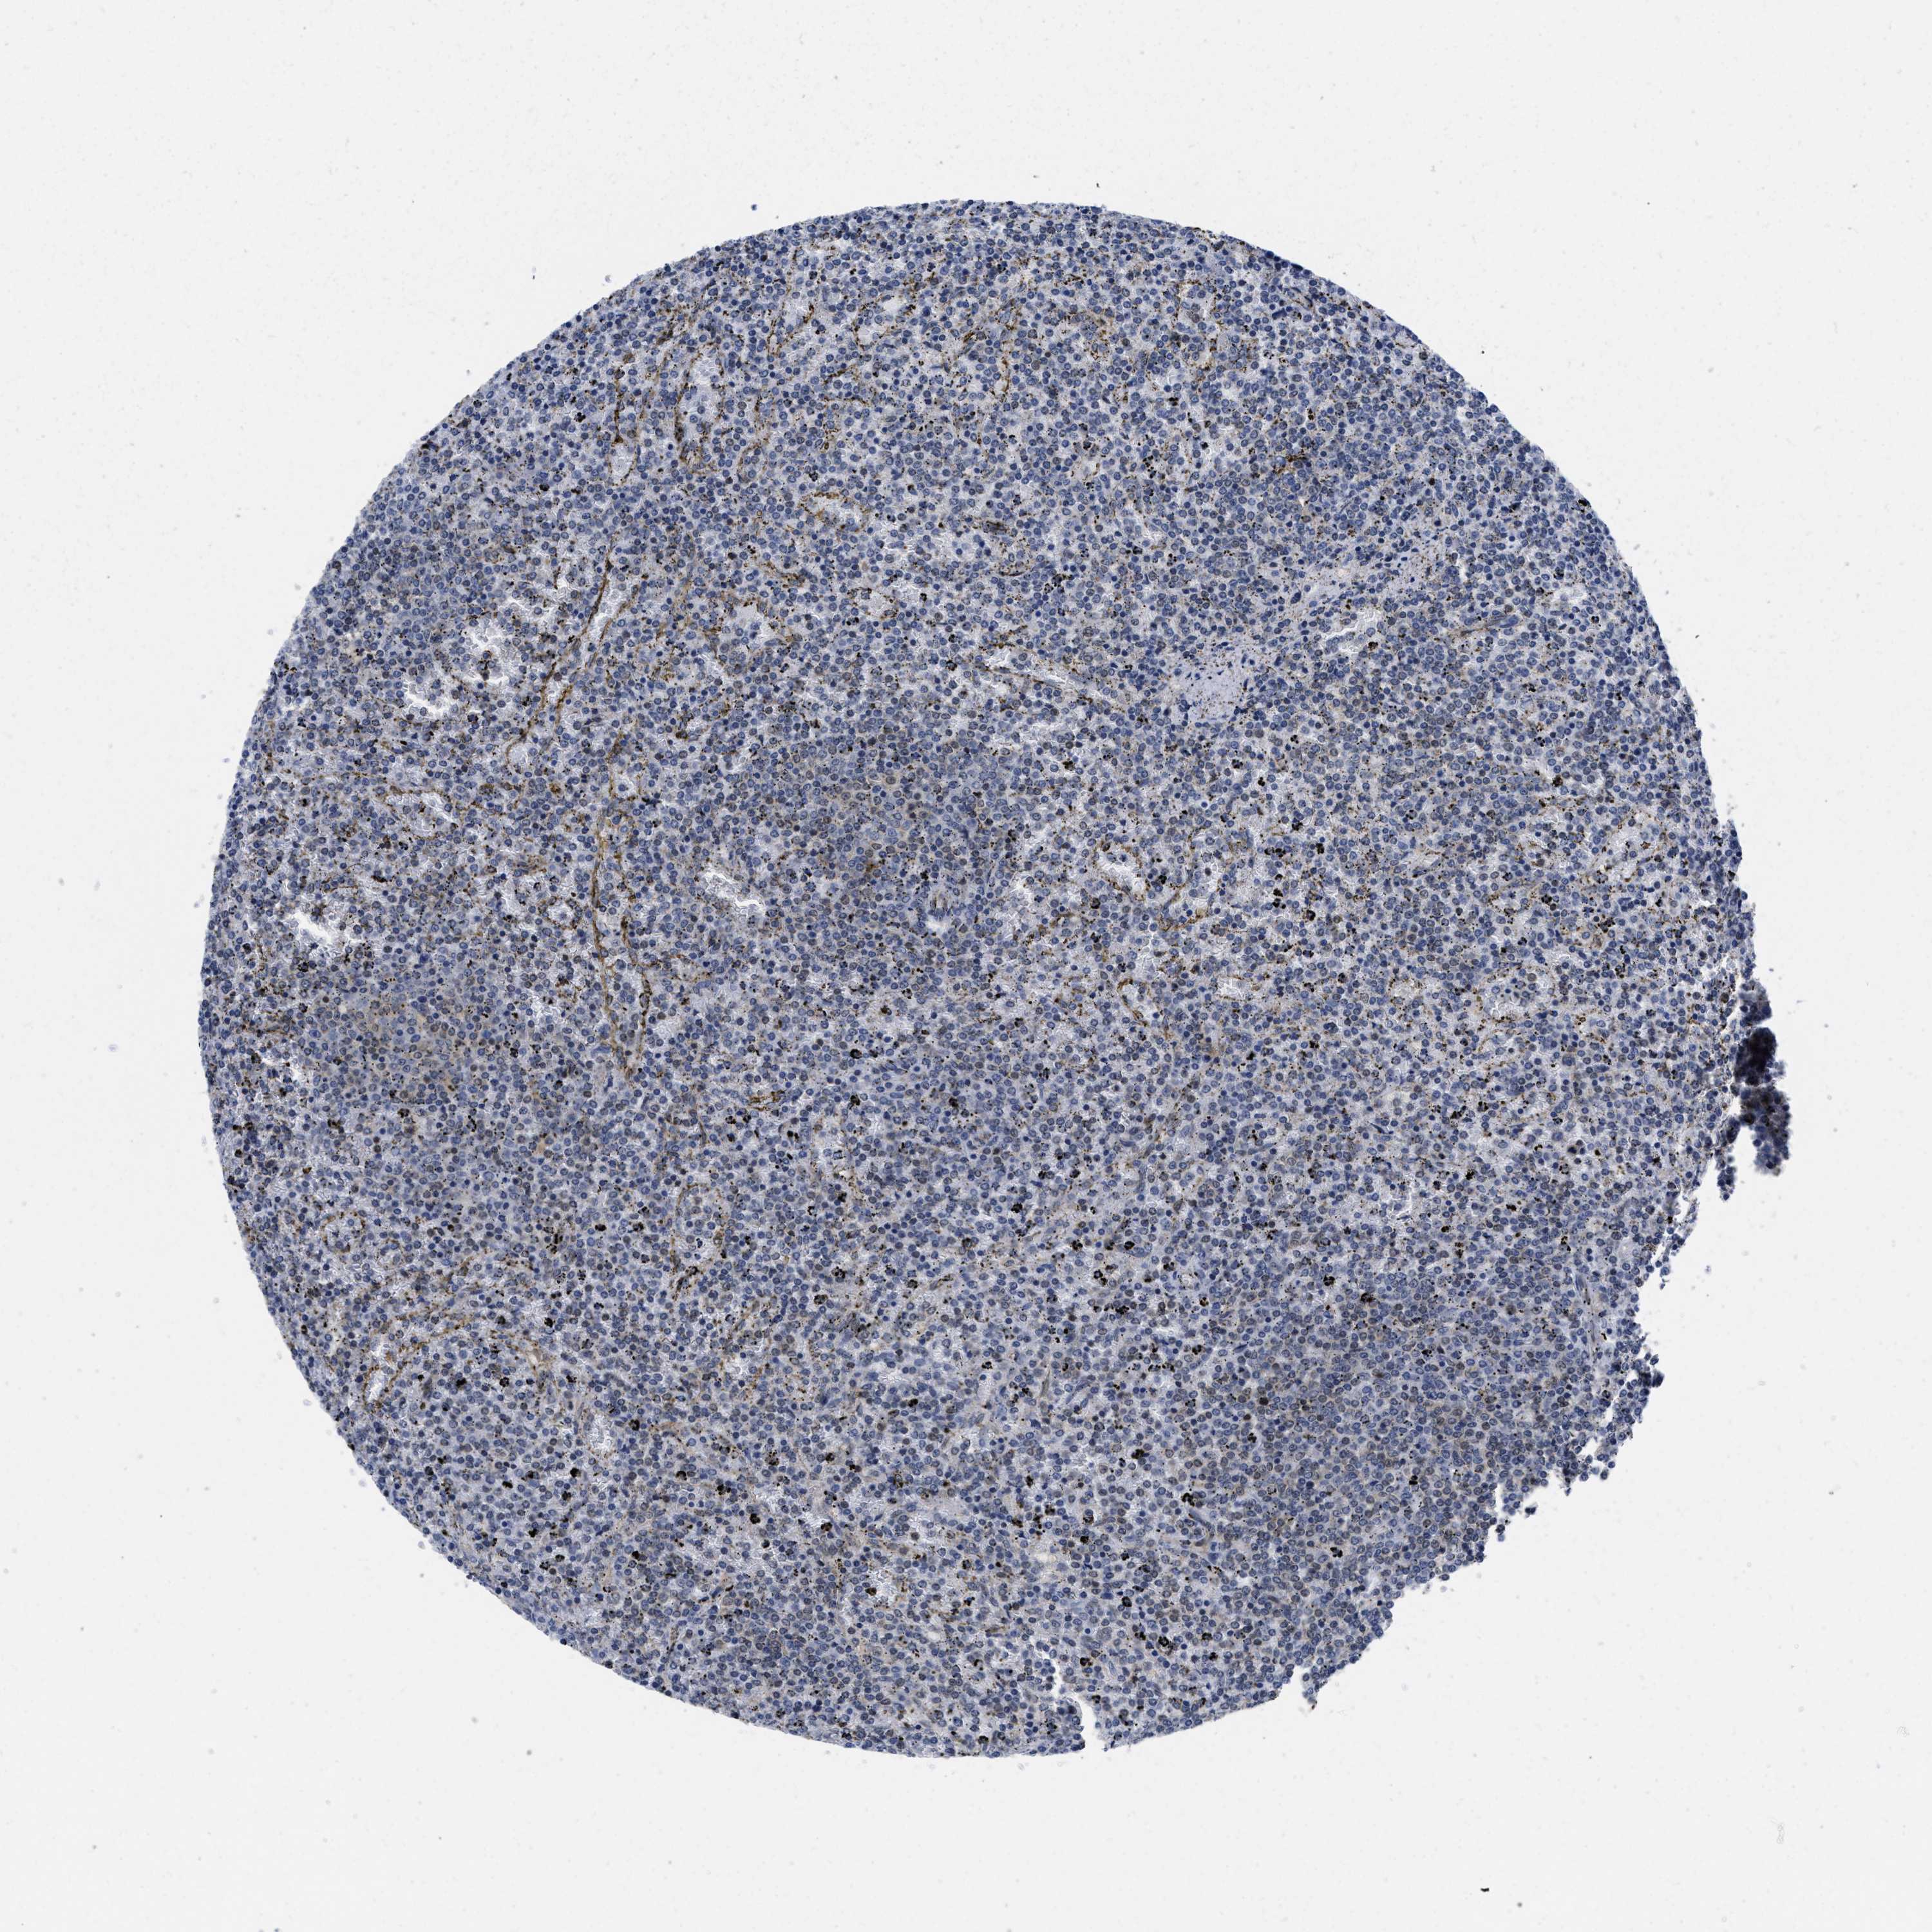

CANCER LYMPHOMA Show tissue menu

LYMPHOMA - Protein expressioni

A mouse-over function shows sample information and annotation data. Click on an image to view it in a full screen mode. Samples can be filtered based on level of antibody staining by selecting one or several of the following categories: high, medium, low and not detected. The assay and annotation is described here.

Each image is clickable and will lead to virtual microscopy that enables deeper exploration of all samples and also displays staining intensity scores, fraction scores and subcellular localization as well as patient and tissue information for each sample.

Antibody HPA001275

Antibody CAB017442

Malignant lymphoma, non-Hodgkin's type, High grade

Hodgkin's disease, NOS

Malignant lymphoma, non-Hodgkin's type, Low grade